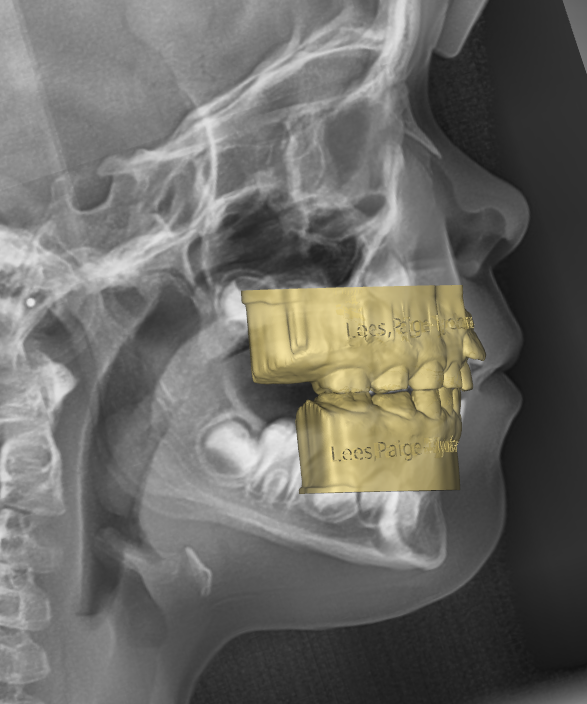

1st Review – 2023-03-01

- YELLOW = Initial 2022-10-29

- BLUE = 1st Review 2023-03-01

Great compliance in the first quarter. Evidence of arch expansion at the molar level.

2nd Review–2023-05-30

- YELLOW = Initial 2022-10-29

- BLUE = 2nd Review2023-05-30

Expansion maintained. Note eruption of the 16